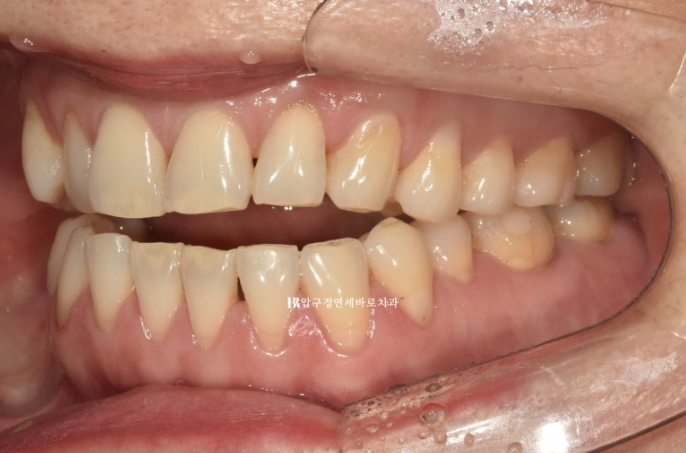

23.05~23.12

걱정하시는 교합도 잘 마무리 되었습니다.

추가장치의 목적은 미세하게 안 맞는 중심선을 맞추고 교정 후 어느정도 재발될 것을 예상해서 살짝 과개교합 상태를 만들어 놓는 것입니다.

아마 추가장치로 3개월 정도면 마무리 될 듯 합니다.

1차세트 7개월 소요되었고 추가장치 3개월이 걸린다면 총 치료기간은 10개월입니다.